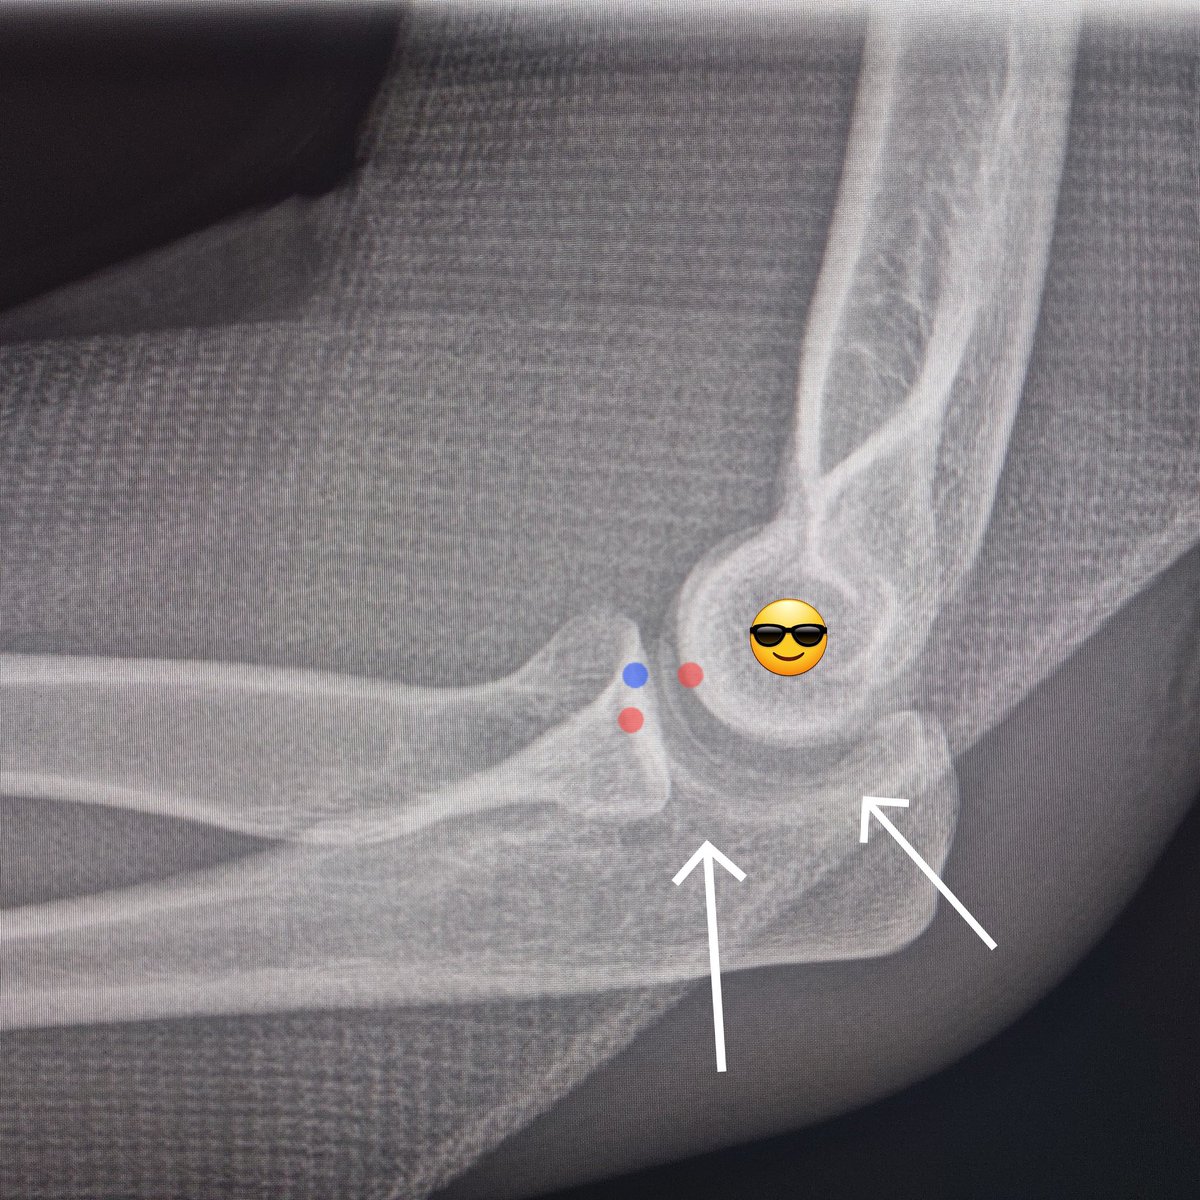

بالتدقيق في الأشعة بعد إعادة المفصل، يلاحظ ان المفصل غير مترابط بشكل صحيح (اتساع المفصل) مما يدل على اصابة في الأربطة